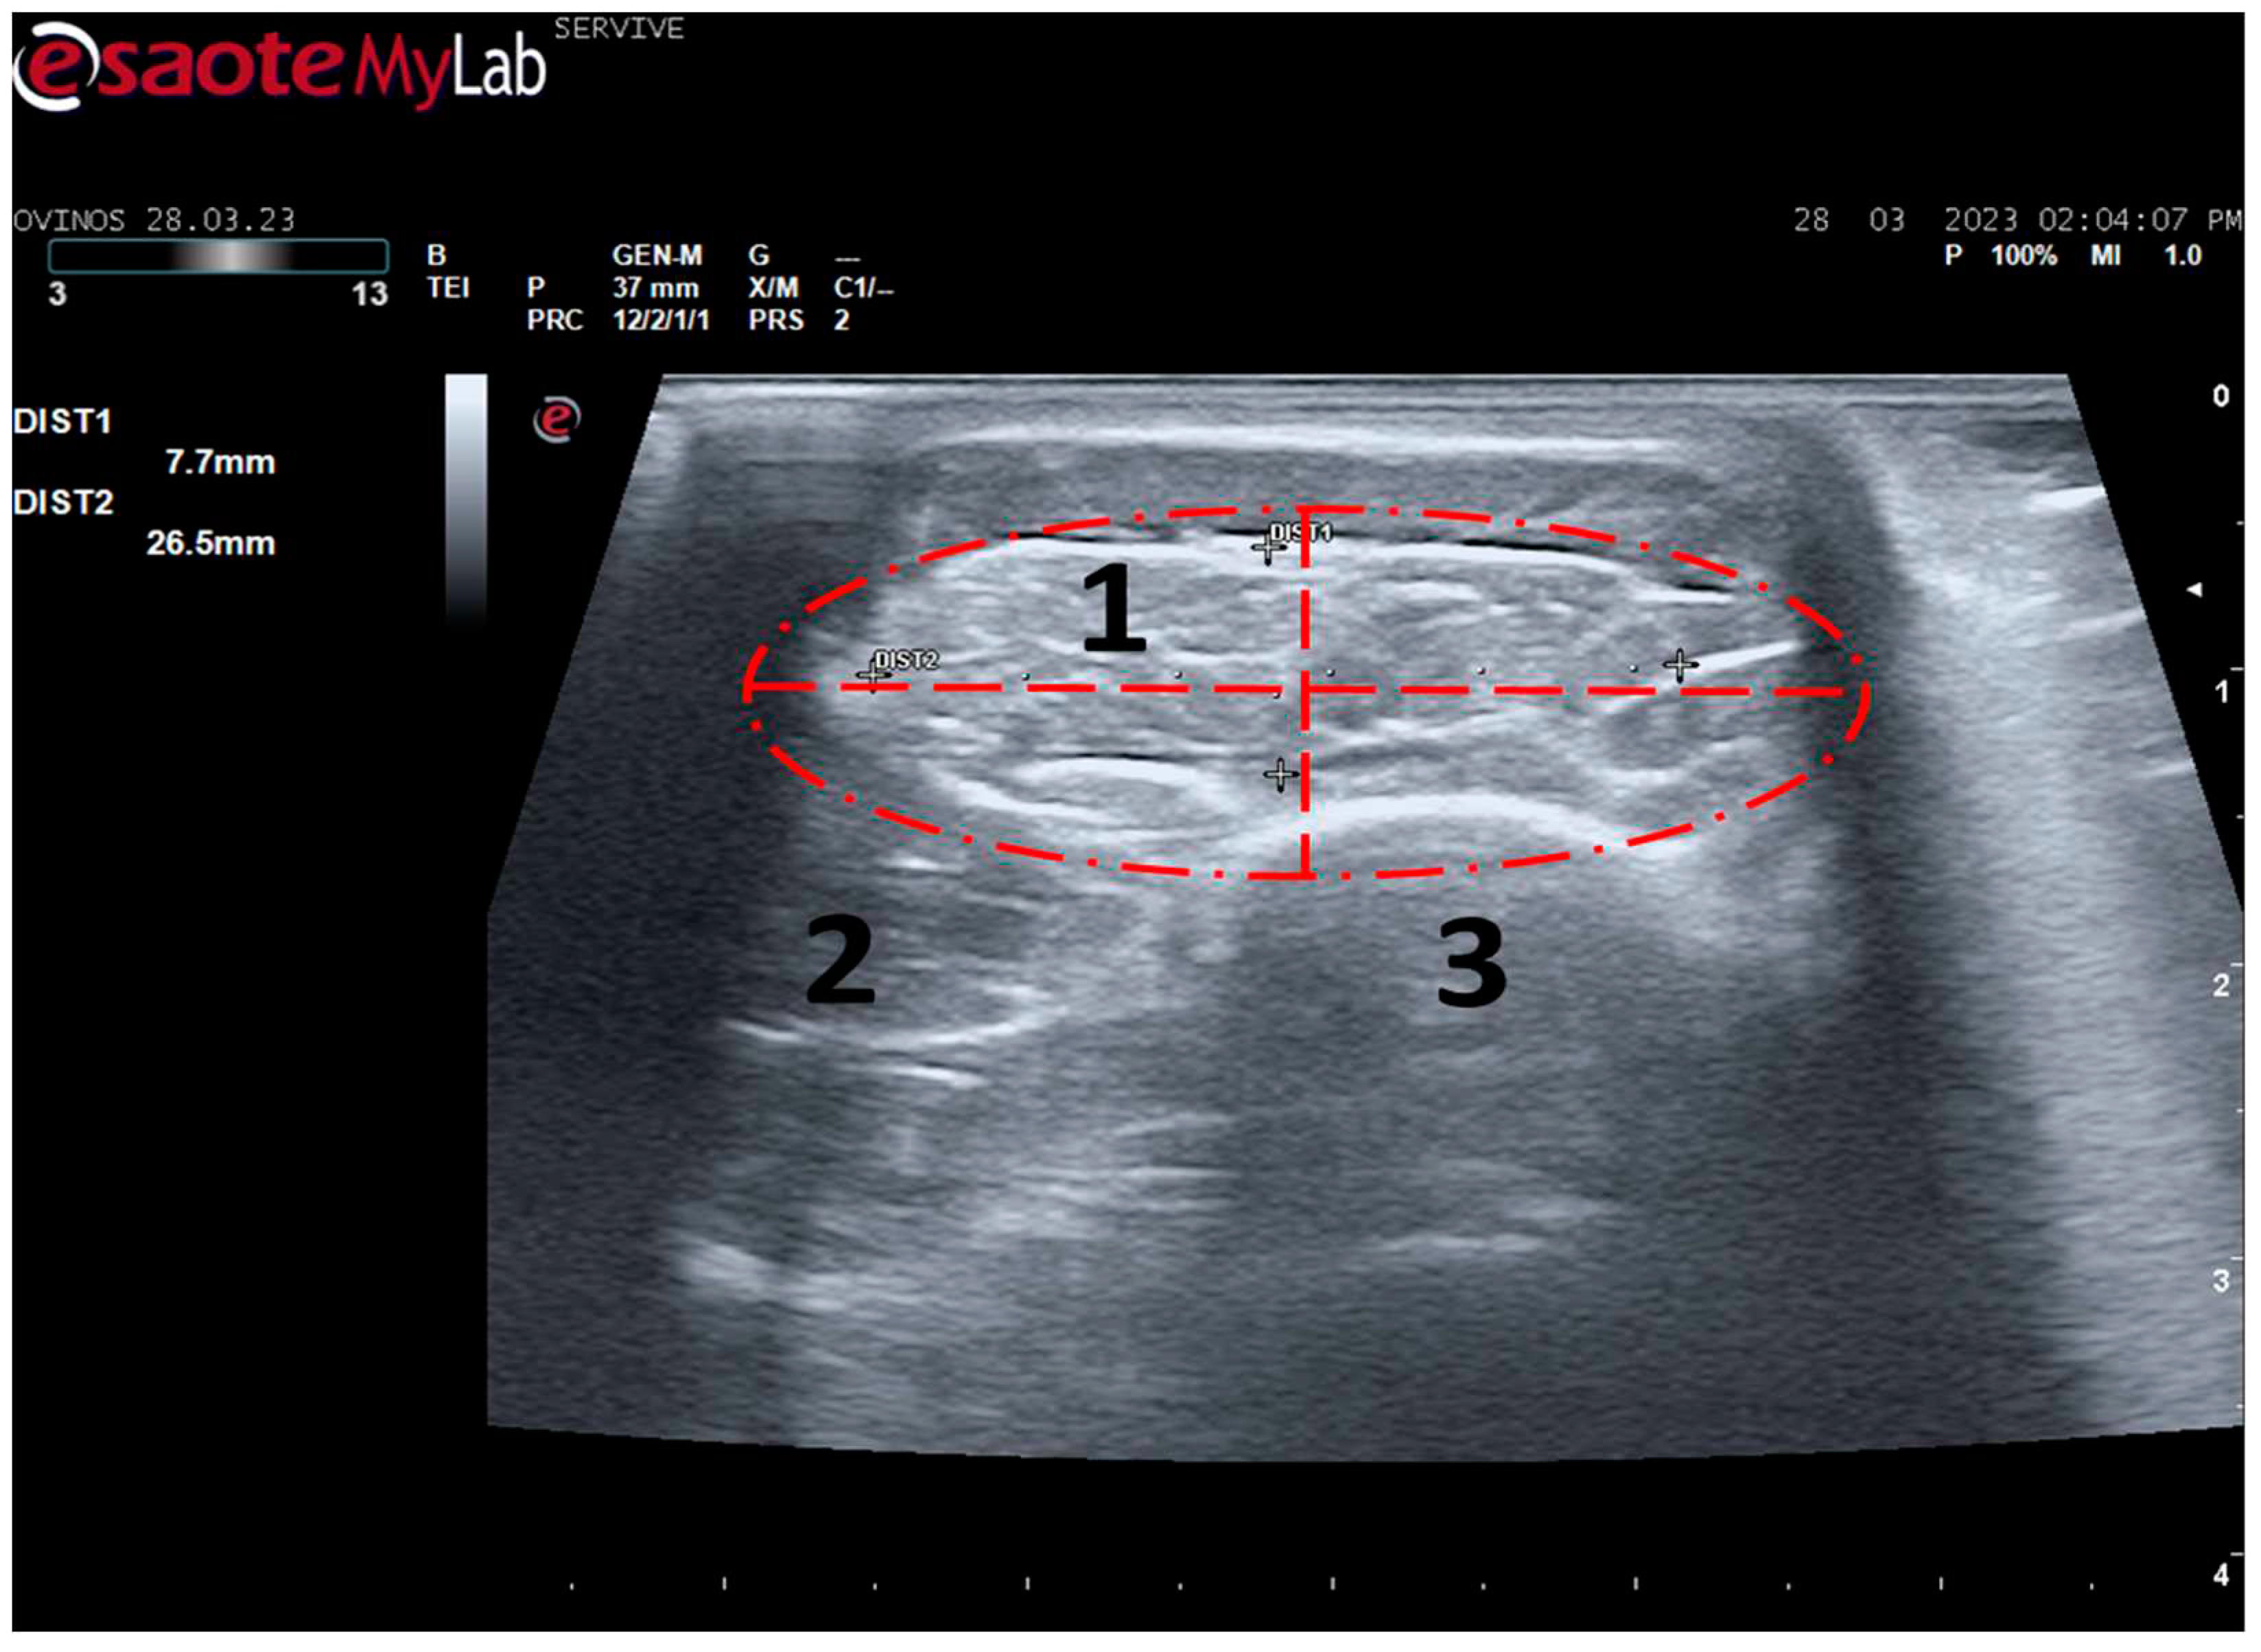

Figure 7.

Ultrasound image of the left cranial tibial muscle taken close to its origin, bounded by dashed circle. 1) tibialis cranialis muscle; 2) extensor digitorum longus muscle; 3) tibia. DIST1 and DIST2 represent the thickness and width of the muscle, respectively.